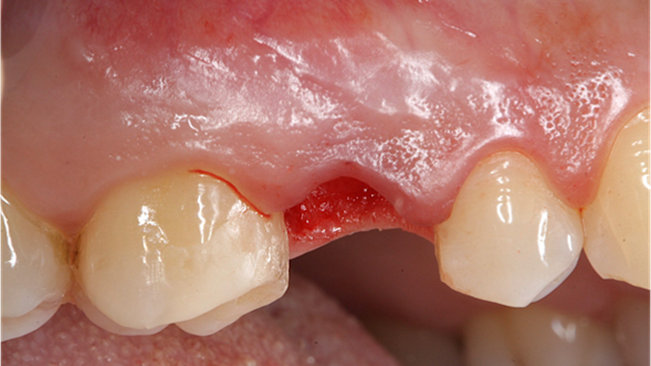

Clinical case: Extraction, immediate implant placement, & provisionalization

- Courtesy of Dr. Iulian Filipov, Romania -

Keywords

AnyRidge, R2GATE, guided surgery, immediate placement, immediate provisionalization, initial stability, Dr. Iulian Filipov, #25, maxillary posterior, immediate loading, Mega ISQ